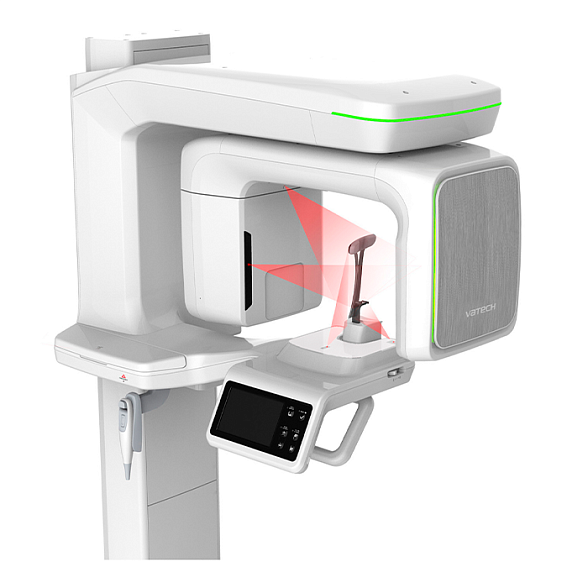

Instrumentarium OP 3D Vision V8 - панорамный томограф

Instrumentarium OP 3D Vision V8: Новый стандарт в панорамной и 3D-диагностике

Панорамный томограф OP 3D Vision V8 от финского бренда Instrumentarium — это современный цифровой аппарат, созданный для комплексной диагностики в стоматологии и челюстно-лицевой хирургии. Он объединяет проверенную надежность, интуитивно понятное управление и передовые технологии визуализации, чтобы предоставить врачу всю необходимую информацию для постановки точного диагноза и планирования лечения.

Ключевое преимущество OP 3D Vision V8 — это универсальность. Один аппарат позволяет выполнять как классические панорамные снимки (ОПТГ), так и детализированные 3D-исследования (КЛКТ) различных областей, включая височно-нижнечелюстные суставы (ВНЧС) и верхнечелюстные пазухи. Это делает его идеальным решением для клиник, стремящихся оптимизировать пространство, бюджет и диагностические возможности.

Внедрение OP 3D Vision V8 в практику приносит ощутимые преимущества как для врача, так и для пациента:

- Всесторонняя диагностика на одном устройстве: Откажитесь от необходимости направлять пациента в другие центры для 3D-снимков. Проводите полный цикл диагностики — от общего обзора до прицельного 3D-анализа — в своем кабинете.

- Высокая детализация изображений: Получайте четкие и контрастные снимки с минимальным уровнем шумов. Это критически важно для оценки анатомии каналов, обнаружения скрытых патологий, планирования имплантации и эндодонтического лечения.

- Снижение лучевой нагрузки: Современные технологии цифрового сенсора и интеллектуальные режимы сканирования позволяют получать качественные изображения при минимально необходимой дозе облучения, заботясь о безопасности пациента.

- Эффективность и скорость работы: Быстрая подготовка пациента, короткое время сканирования и мгновенная реконструкция данных экономят время врача и повышают пропускную способность кабинета.

- Удобство для пациента: Комфортное положение стоя, фиксация головы и подбородка, а также быстрая процедура минимизируют дискомфорт и тревожность, что особенно важно для детей и пожилых людей.